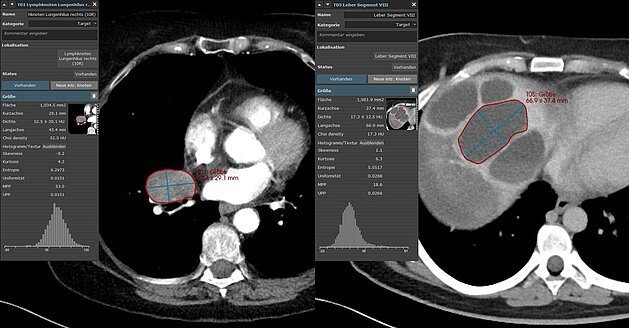

A recent prospective study [1] conducted by researchers at Cincinnati Children’s Hospital Medical Center compared manual 2D, semi-automated 2D, and…